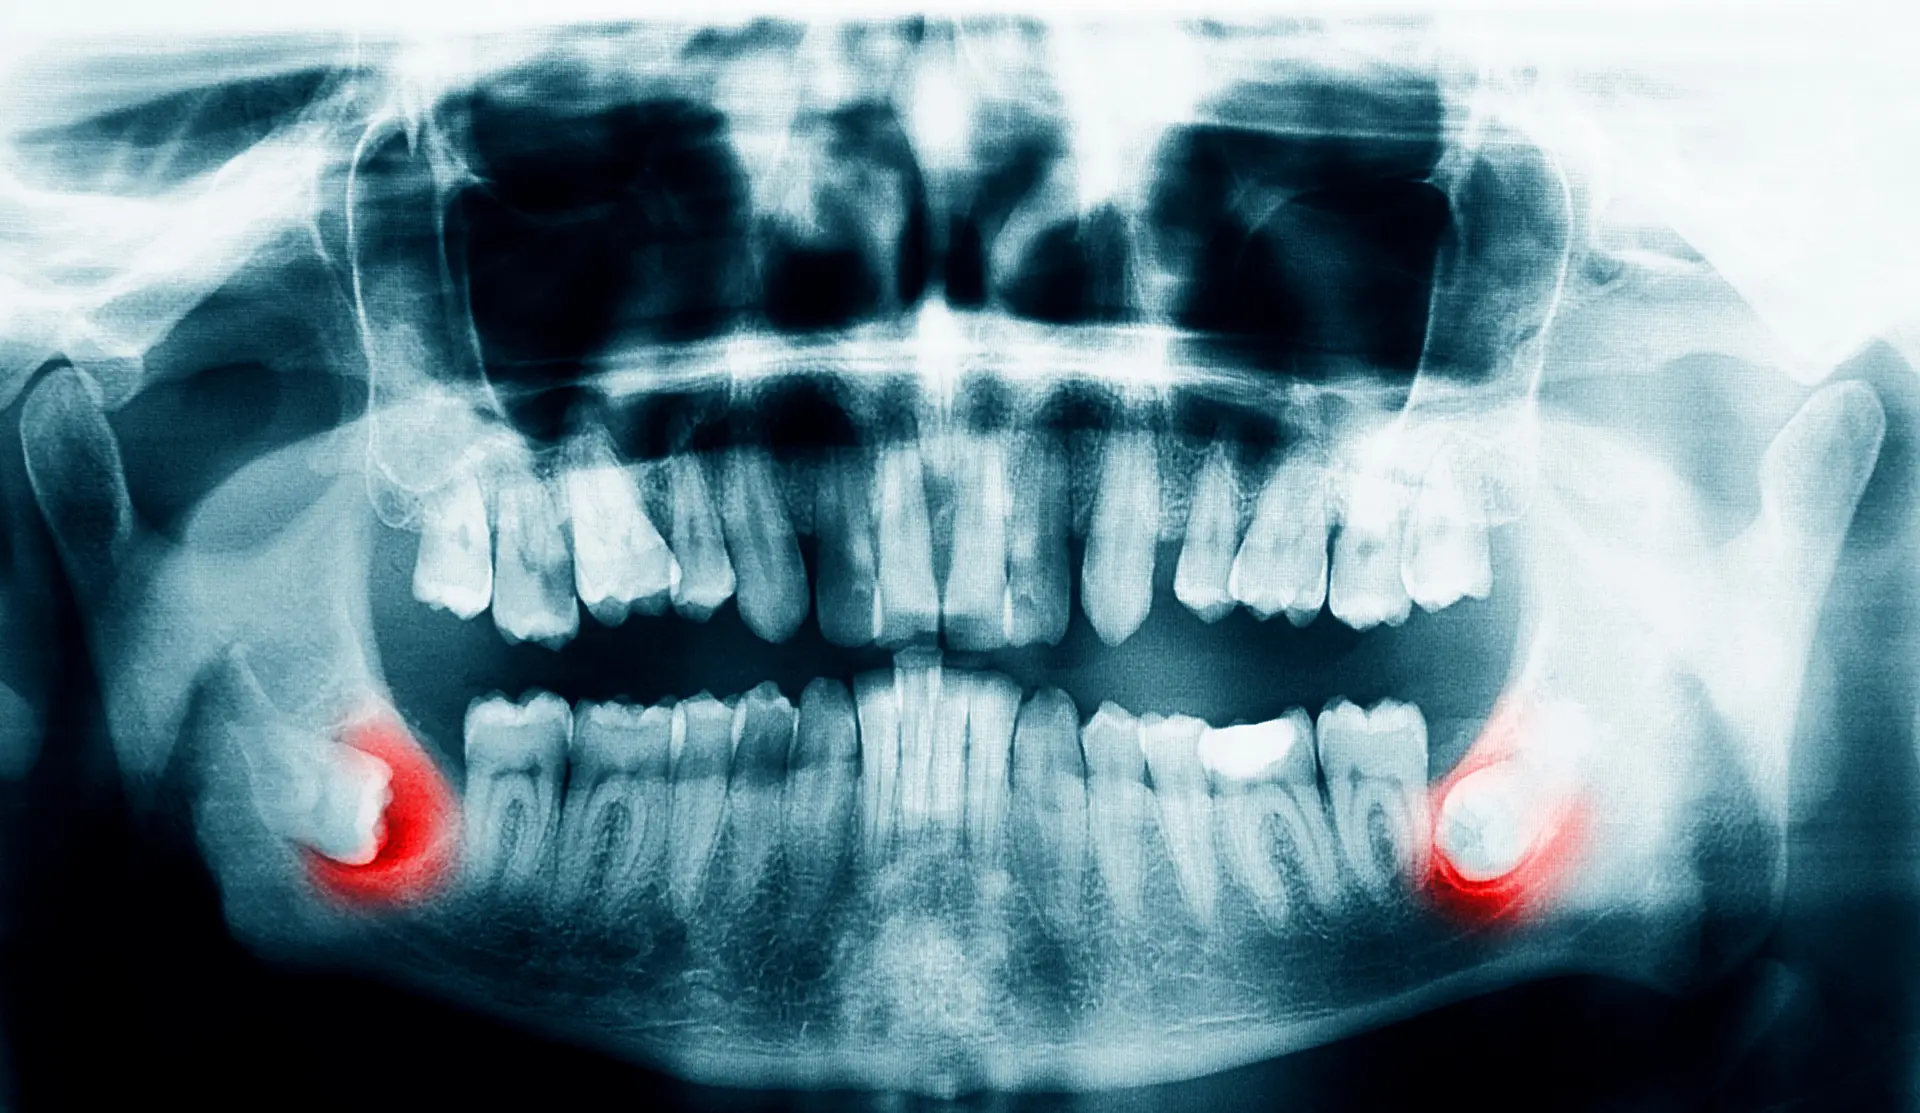

Diagnostic Imaging

To get a complete picture, diagnostic imaging is necessary. We typically use a Cone Beam CT (CBCT) scan, which provides a detailed 3D view of your wisdom teeth, jawbone, and surrounding anatomical structures. This is a critical step because it allows us to precisely identify the location of important nerves, like the inferior alveolar nerve, and understand the tooth's relationship to adjacent molars. This information is vital for planning a safe and predictable surgical procedure.

Risk and Benefit Analysis

The oral surgeon evaluates the diagnostic imaging to determine the complexity of the extraction. They will identify potential risks, such as proximity to nerves or sinuses, and discuss the indications for removal, such as preventing pain, infection, or damage to other teeth. They will also discuss the benefits of extracting the wisdom teeth versus leaving them in place.